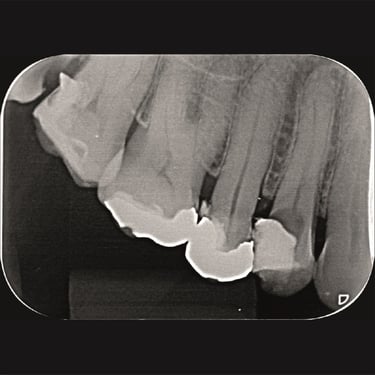

CASOS CLÍNICOS ENDO

Abaixo você encontra fotos de alguns dos tratamentos realizados.